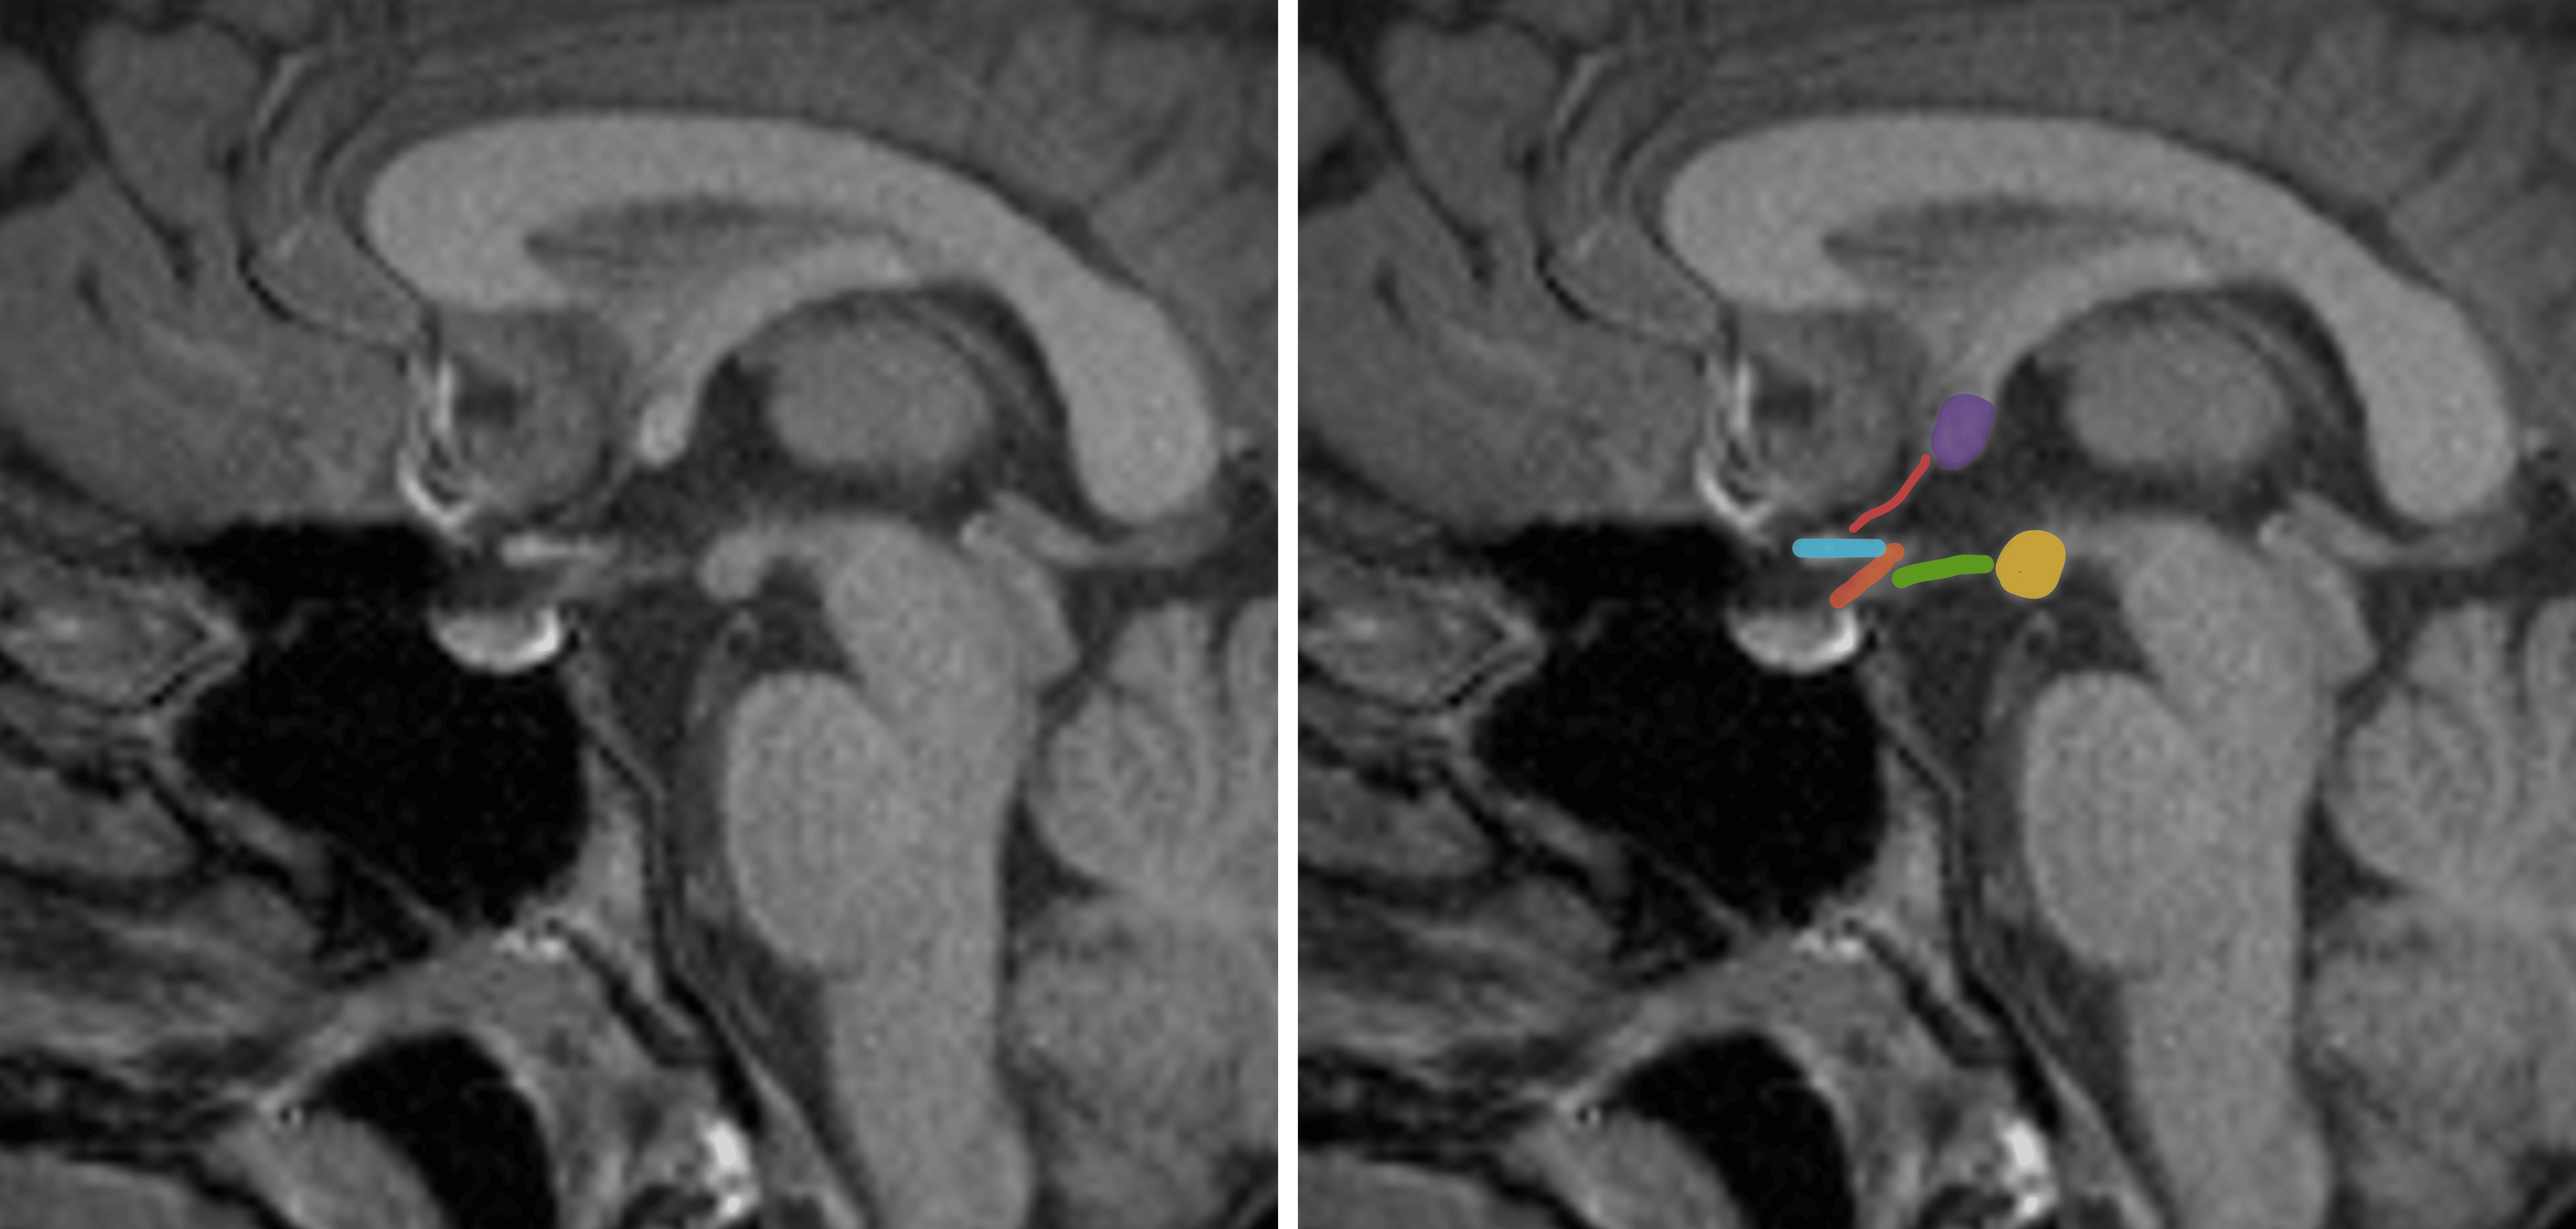

Relevant anatomic structures on a midline sagittal image in and around the hypothalamus: purple - anterior commissure, pink - lamina terminalis, blue - optic chiasm, orange - pituitary infundibulum, green - tuber cinereum, yellow - mammillary body.